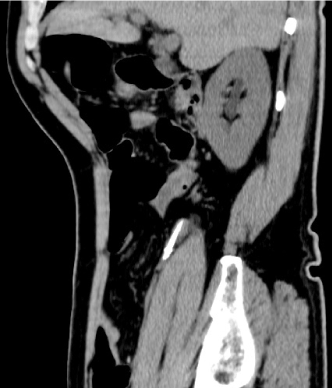

A 77-year-old man was referred to our hospital following ingestion of a dental drill bit. He was asymptomatic and had no abnormal findings on physical assessment or blood tests. We performed esophagogastroduodenoscopy but could not locate the drill bit. The next day, an abdominal radiograph showed the drill bit in the right lower abdominal quadrant. Two days later, we performed colonoscopy because the drill bit had not moved on the radiograph. However, we could not locate the drill bit. Subsequent CT examination revealed the drill bit within the appendix (Figure 1). Colonoscopy under fluoroscopic guidance showed the drill bit in the appendix, which was crookedly oriented (Figure 2). We unsuccessfully attempted to straighten the appendix with an endoscopic retrograde cholangiopancreatography catheter and endoscopically remove the drill bit. Although the patient was asymptomatic, laparoscopic appendectomy was performed. Pathological examination showed a 35-mm drill bit within the appendix (Figure 3), and histological examination showed only mild inflammation. The patient was discharged with no postoperative complications.

Figure 1. CT (sagittal view) showed the drill bit in the appendix.